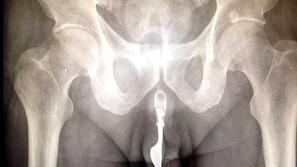

V svoj penis vstavil vilico?!

Neki 70-letni Avstralec je v svoj penis vstavil vilico in pristal v mednarodno priznani strokovni reviji o kirurgiji In…